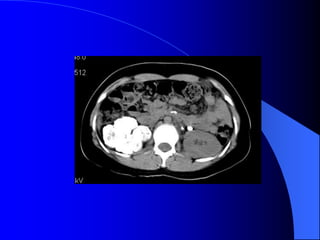

4.1. U nhumä tháûn - Carcinome tãú baìo tháûn Ung thæ tháûn chiãúm 3% ung thæ caïc loaûi åí ngæåìi låïn, 95% trãn 50 tuäøi, nam gáúp âäi næî. Yãúu täú thuáûn låüi laì tháûn âa nang, suy tháûn kãút håüp âa nang màõc phaíi, tháûn dë daûng hçnh moïng ngæûa, nghiãûn thuäúc laï. Caïc loaûi u aïc tênh khaïc åí tháûn nhæ di càn, lymphome, caïc loaûi sarcome, u nguyãn baìo tháûn åí ngæåìi låïn.

- Siãu ámphán biãût âæåüc khäúi âàûc vaì dëch. Nãúu laì khäúi âàûc seî xem xeït cáúu truïc ám, coï thãø giaím, âäöng hoàûc tàng ám, xem âäü âäöng nháút ám, väi hoïa. Nãúu laì khäúi dëch, seî tçm täø chæïc âàûc hoàûc vaïch trong nang. Siãu ám coï thãø tháúy haûch di càn, xám láún ténh maûch. Noïi chung khi phaït hiãûn khäúi âàûc trãn siãu ám, cáön chuûp CLVT âãø âaïnh giaï roî hån baín cháút, sæû xám láún, di càn.

- CLVT phánbiãût khäúi âàûc hay dëch, phaït hiãûn väi hoïa nhoí, xuáút huyãút trong u, tçnh traûng tæåïi maïu cuía u. Pháön låïn træåìng håüp phán biãût âæåüc u laình vaì u aïc. Xem xeït âæåìng dáùn niãûu bë giaîn, bë xám láún. CLVT kiãøm tra di càn haûch xám láún vuìng xung quanh, xám láún maûch maïu, di càn xa, cå såí âãø phán giai âoaûn tiãún triãøn u, cáön thiãút cho phæång phaïp âiãöu trë.